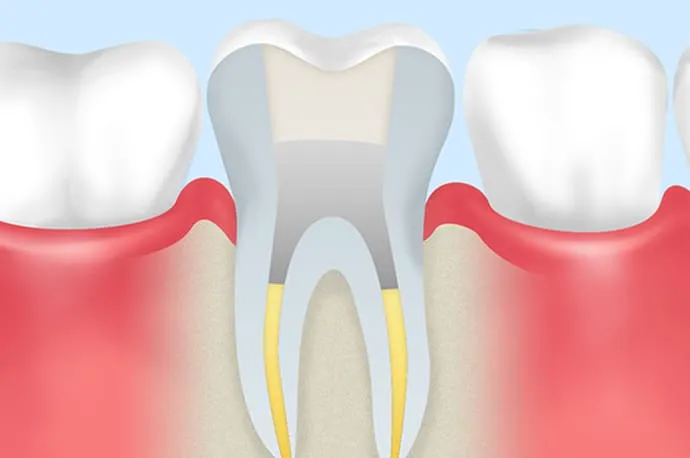

3.きれいな根管を維持する

根管内を清潔な状態にできたら、その環境を長く保つことが重要です。防腐作用のある材料やバイオセラミック系の糊材で根管内をすき間なく満たし、再び細菌が侵入しないようにします(根管充填)。

また、治療後に装着する被せ物の精度も非常に重要です。適合の良い被せ物を装着することで、細菌の侵入を防ぎ、治療の成功率を高めることにつながります。

STEP 06

根管充填と土台作り

再来院時に問題がなければ、根管内に防腐剤の詰め物を行います(根管充填)。その後、感染を防ぐため、歯と強力に接着するレジンなどの材料で上からフタをし、歯の土台を作ります(築造)。

その後は、できるだけ早めに型採りを行い、仮歯や最終的な被せ物を作製していく流れとなります。